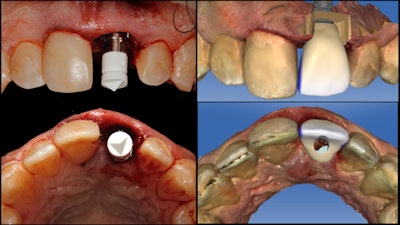

After a six-month period to allow the patient's soft tissue to heal and the implant to integrate, the patient returned to the office for re-evaluation. At that point, the original provisional design was modified to full-emergence contours, brought into occlusion, and modified from a screw-retained restoration into a split design with a separate IPS e.max CAD (Ivoclar Vivadent) custom abutment and an abutment-supported implant crown.

The restorative components were then milled on the MCXL, crystallized in a Programat P500 furnace (Ivoclar Vivadent), and characterized using stain and glaze. The abutment was then bonded onto a TiBase (Dentsply Sirona) (figure 6).

Finally, tooth #8 was prepared for a crown restoration. The tooth was imaged, and the crown was designed and milled so that both restorations could be delivered simultaneously to complete the entire surgical and restorative process in only two clinical visits (figure 7).